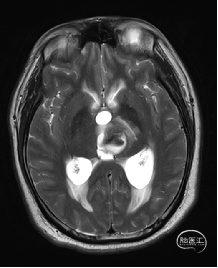

术前MRI检查

术前MRI检查提示左侧丘脑中脑海绵状血管瘤并卒中,梗阻性脑积水;

诊断:1.左侧丘脑中脑海绵状血管瘤并卒中,2.梗阻性脑积水;

年轻患者,较短时间内发生左侧丘脑二次出血,出现右侧面部及上肢麻木,复视,第二次出血后并发梗阻性脑积水,出现头痛。结合病史、神经系统体征、头颅CT及MRI检查,诊断左侧丘脑及中脑CM并卒中、脑积水明确,并导致了神经功能障碍,具备手术指征。

根据MRI及DTI显示,只有在丘脑与上丘之间的点(dot)进入病变才可能在切除病变时最大程度保护神经功能,由于上述原因,该“点”在术中显露极其困难,虽有导航指引,电生理监测的条件下,对术者的耐心、技术、经验及体能依然是极大的挑战;

本例患者磁共振检查清晰显示病变位于左侧丘脑中脑区域,且位于丘脑内下方向中脑顶盖延续,病变的上部、前部、外侧部都有重要的神经组织,因此,手术从上方、前方、外侧方向切除病变均难以实施;